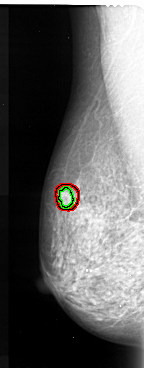

A_1025_1.RIGHT_MLO

RIGHT_MLO LINES 5491 PIXELS_PER_LINE 2131 BITS_PER_PIXEL 16 RESOLUTION 42 NON_OVERLAY

ABNORMALITY 2

LESION_TYPE CALCIFICATION TYPE PLEOMORPHIC DISTRIBUTION CLUSTERED

ASSESSMENT 5

SUBTLETY 5

PATHOLOGY MALIGNANT

TOTAL_OUTLINES 1

BOUNDARY